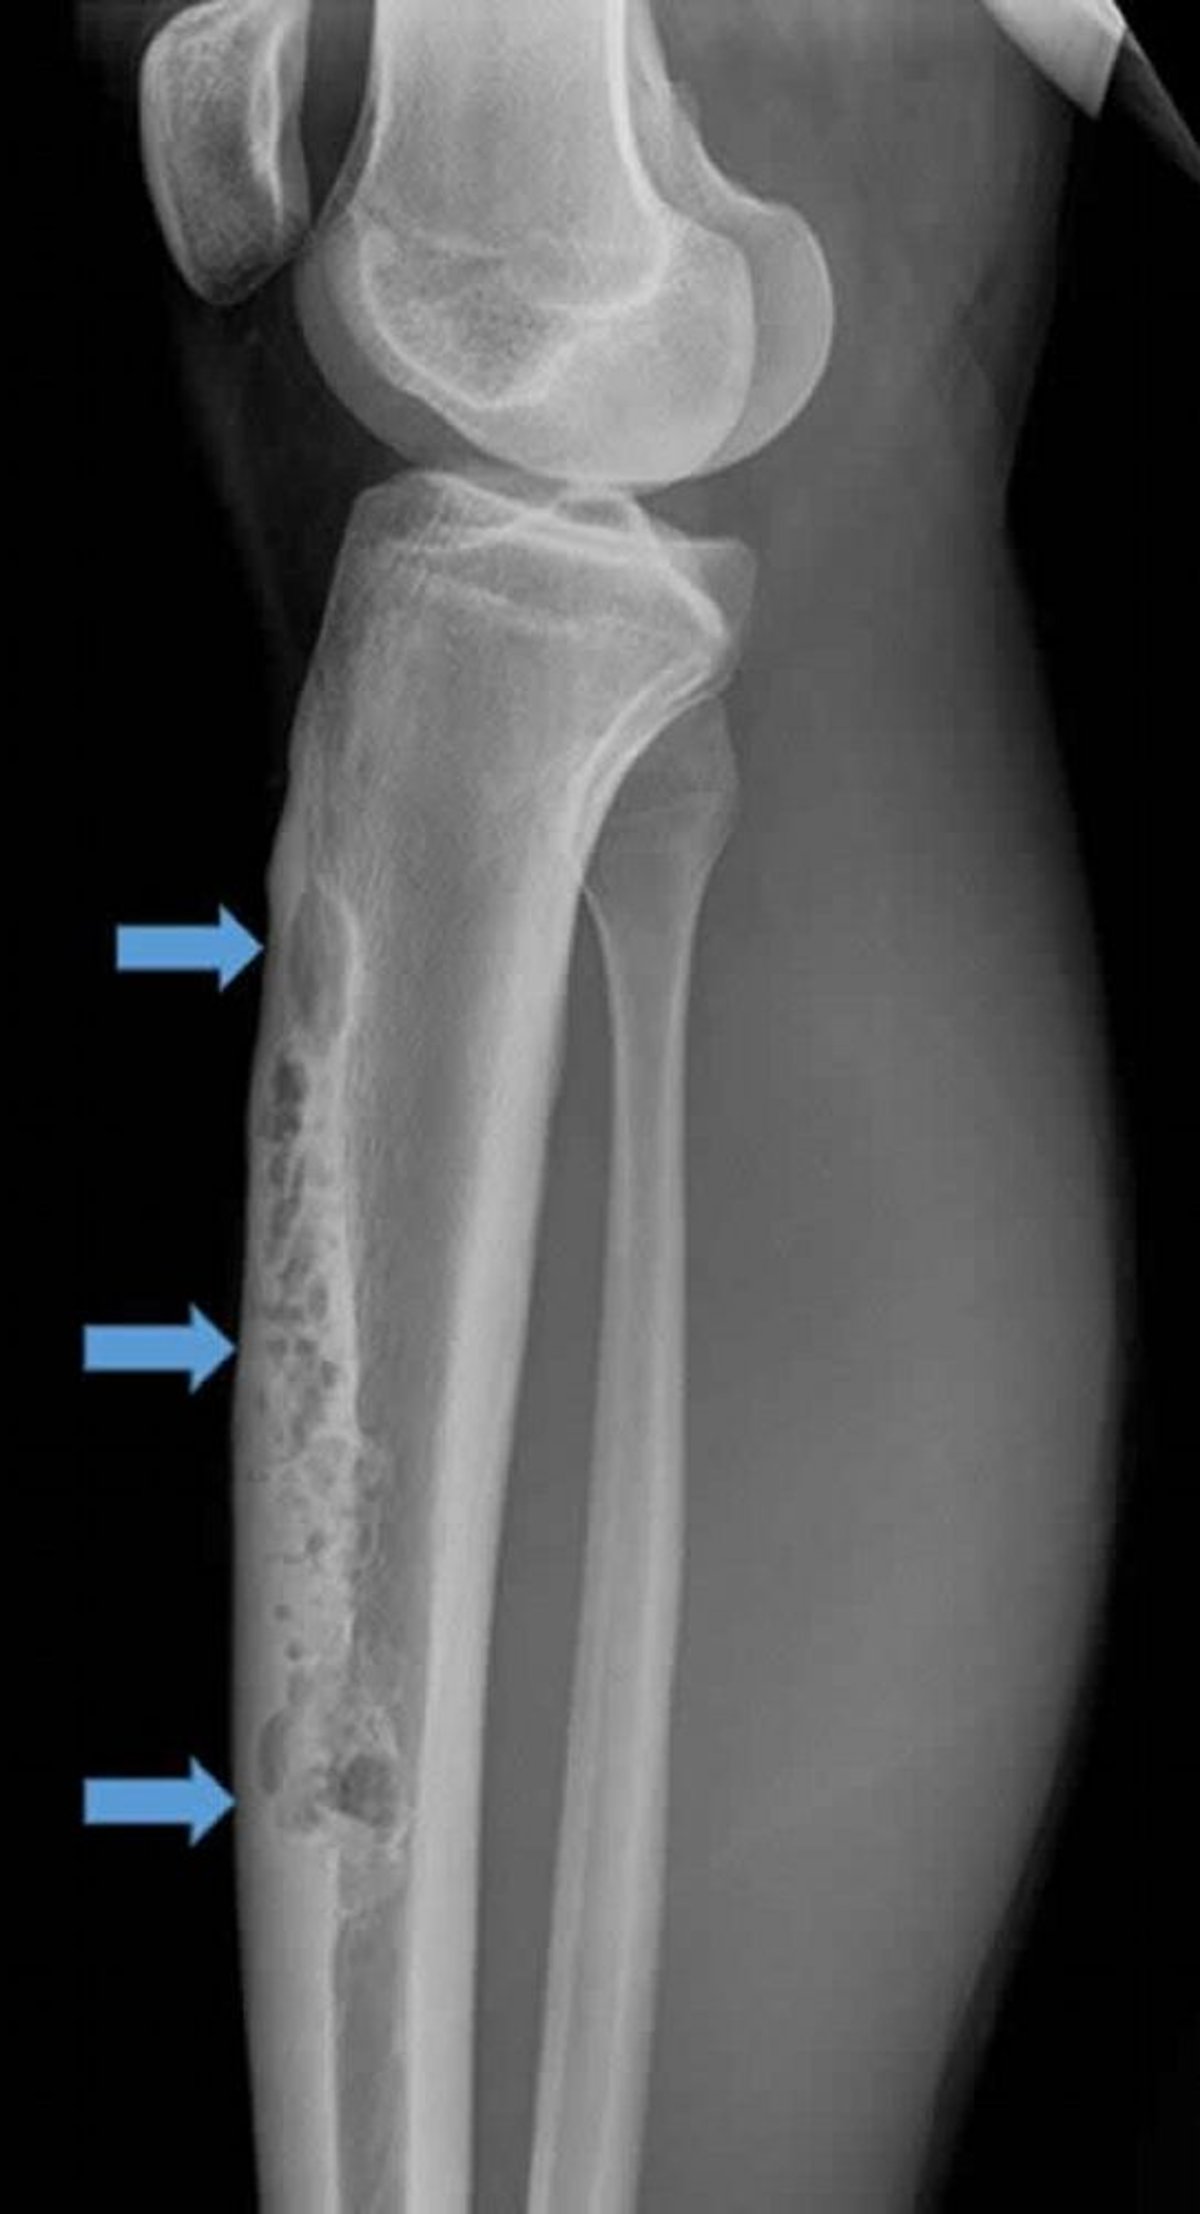

Esta radiografía lateral de la tibia derecha muestra un gran adamantinoma intracortical anterior (flechas). Nótese la apariencia permeativa, osteolítica en "burbuja de jabón".

Image courtesy of Michael J. Joyce, MD, and Hakan Ilaslan, MD.